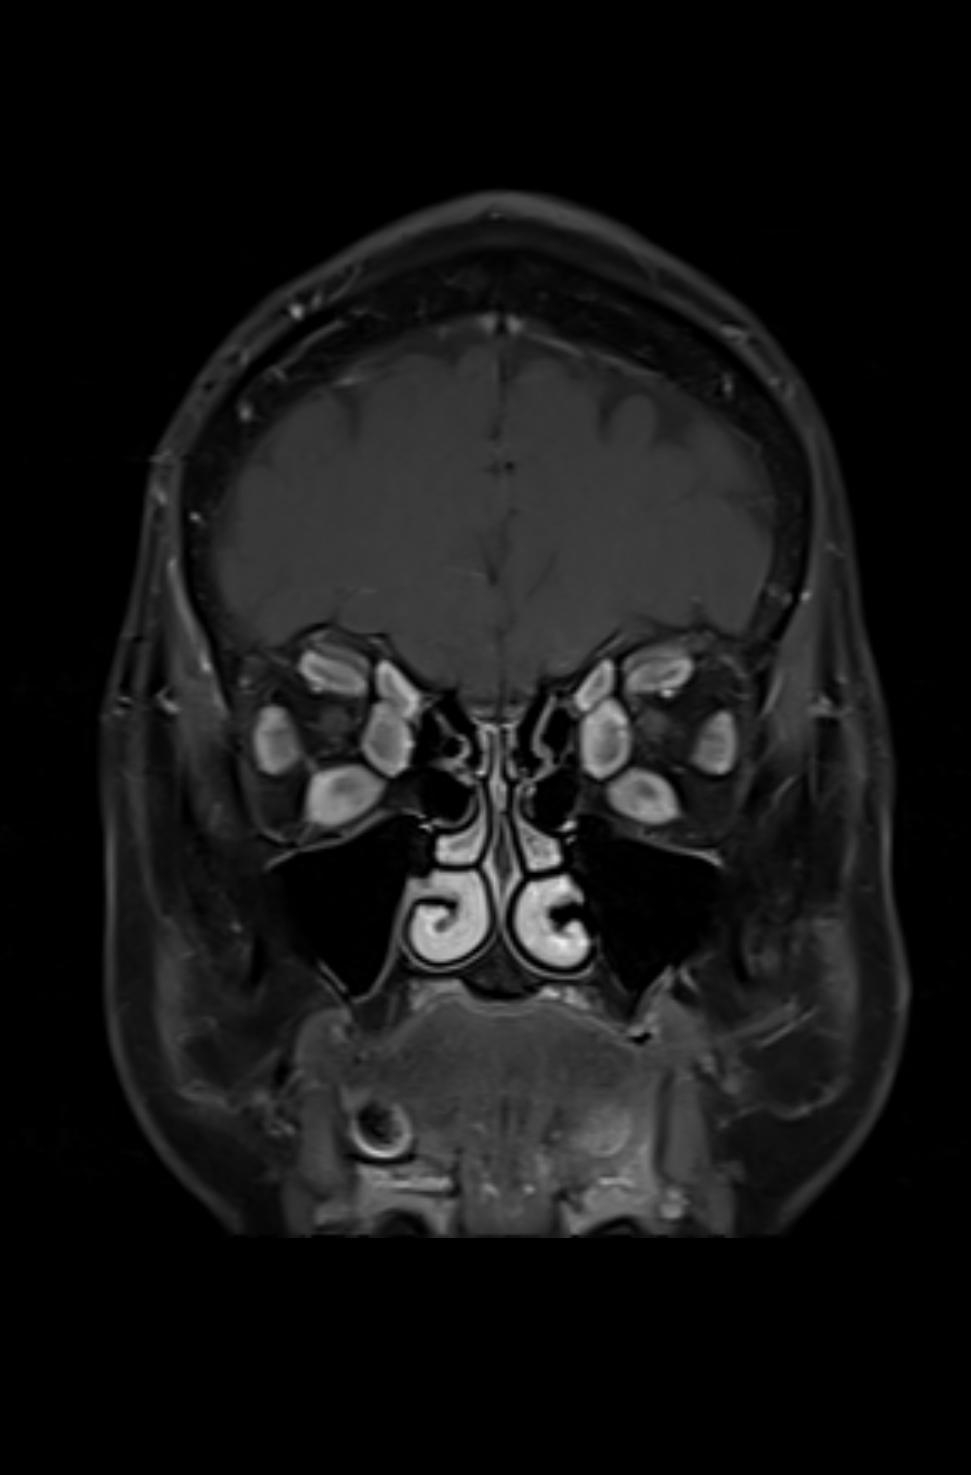

Es zeigen sich die typischen Verdickungen der Muskelbäuche der äußeren Augenmuskeln und ein Exopthalmus (Bild 3-3). In der koronaren, T2-gewichteten Sequenz mit Unterdrückung des Fettsignals (Fettsättigung) zeigt sich ein ausgeprägter Befund der endokrinen Orbitopathie mit Beteilung der Rectus-Muskeln beider Orbitae und einer Beteiligung des Musculus obliquus superior beidseits. Zusätzlich ist ein Ödem im Musculus rectus inferior beidseits, im Musculus rectus lateralis rechts, im Musculus rectus medialis links und im Musculus obliquus superior rechts abgrenzbar (Bild 3-1), welches auf eine akute entzündliche Aktivität deutet.